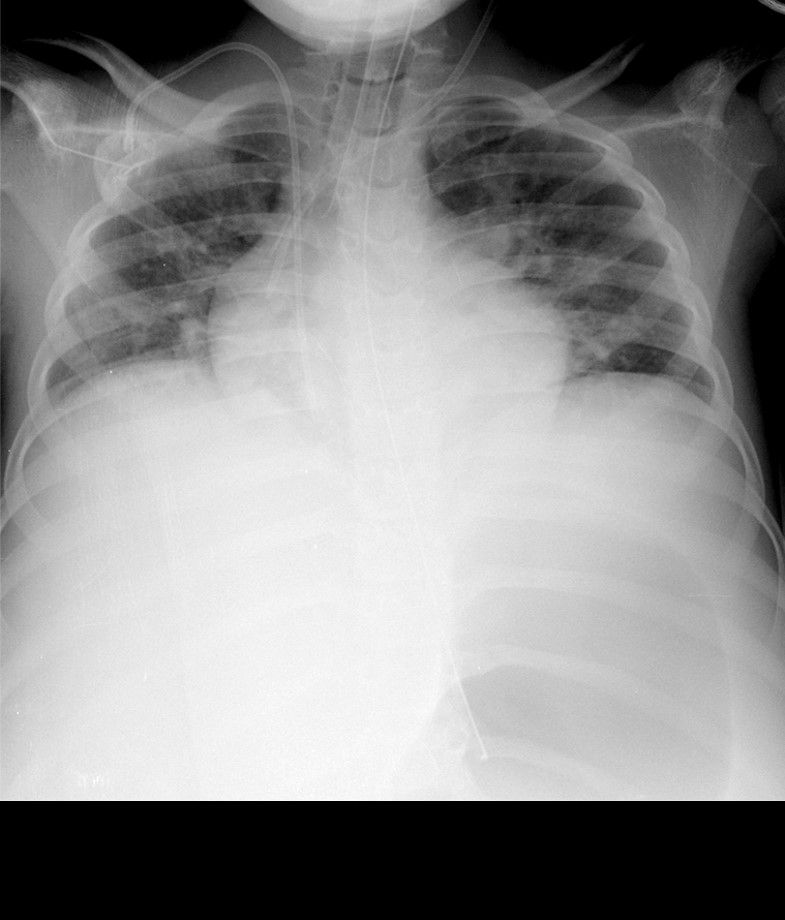

Los catéteres vasculares, centrales o periféricos, así como los tubos endotraqueales, nasogástricos, y drenajes pleurales, se utilizan frecuentemente en el paciente hospitalizado y de forma rutinaria en las unidades de cuidados intensivos.

La radiografía simple permite identificar de posición de los extremos de estos dispositivos, evitando localizaciones inadecuadas y sus complicaciones10.